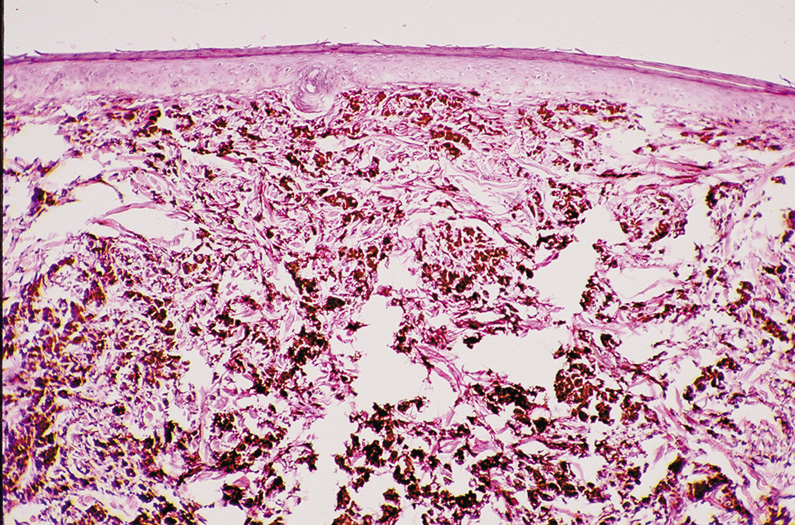

Although no one really dies from old skin, the psychological impact of dry, rough, wrinkled, lax, unevenly pigmented skin around the eyes with a variety of protruding tumors is immense. Skin aging is intrinsic (age related, occurring on non–sun-exposed skin) and extrinsic (predominantly sun induced). The epidermis is usually thin with a disorderly maturation of keratinocytes. The most characteristic histologic finding is a tremendous increase in elastic tissue visualized as basophilic-to-gray staining, amorphous masses in the superficial dermis, often termed basophilic degeneration or solar elastosis (Fig. 17). Accentuating age-related changes may result in an ectropion (turning out) or an entropion (turning in) of the lower lid. Histologically, both show chronic nongranulomatous dense inflammation and scar formation of the skin and conjunctiva. An ectropion shows increased orbicular and Riolan's muscle ischemia, fragmentation of elastic and collagenous tissues in the orbital septum and tarsus, and hypertrophy of the tarsus. An entropion shows increased atrophy of the orbital septum and tarsus. Dermatochalasis is an age-related change manifested by lax, redundant skin of the lids. These folds may even cover the palpebral fissure, thereby impairing vision.

Fig. 17. Actinic (Solar) Elastosis—A. With standard hematoxylin-eosin staining, the areas of sun-damaged collagen stain present a somewhat vermiform appearance and stain more basophilic than the undamaged dermal collagen (hematoxylin and eosin stain). B. The Verhoff-VonGiesen elastic stain stains the damaged collagen like elastic tissue (Verhoff-VonGiesen stain). (Photos courtesy of William Morris, M.D.)